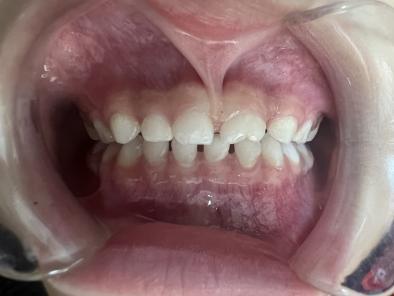

案例一:

治疗后